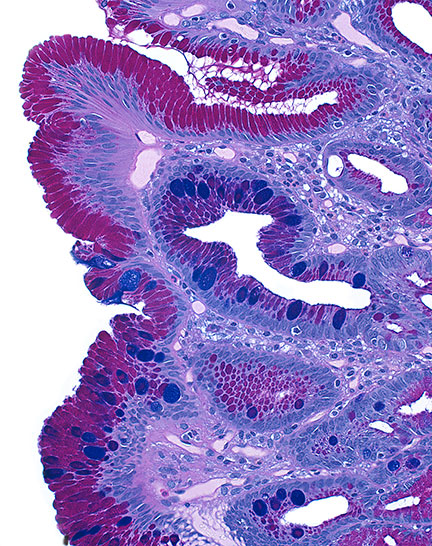

Thirty years later, the medical photographer and associate professor of pathology and art at the Johns Hopkins University’s School of Medicine will tell you that debilitating human diseases can actually be quite photogenic under the microscope, particularly when the professionals studying them use color stains to enhance different shapes and patterns.

“Beauty may be seen as the delicate lacework of cells within the normal human brain, reminiscent of a Jackson Pollock masterpiece, the vibrant colored chromosomes generated by spectral karyotyping that reminded one of our colleagues of the childhood game LITE-BRITE or the multitude of colors and textures formed by fungal organisms in a microbiology lab,” says Christine Iacobuzio-Donahue, a pathologist at the Johns Hopkins Hospital who diagnoses gastrointestinal diseases.

Barker and Iacobuzio-Donahue share in interest in how medical photography can take diseased tissue and render it otherworldly, abstract, vibrant and thought-provoking. Together, they collected nearly 100 images of human diseases and other ailments from more than 60 medical science professionals for Hidden Beauty, a book and accompanying exhibition. In each image, there is an underlying tension. The jarring moment, of course, is when viewers realize that the subject of the lovely image before them is something that can cause so much pain and distress.

Here is a selection from Hidden Beauty: